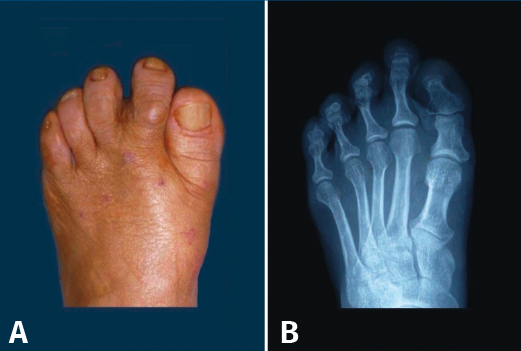

El año 2017 A. Isidro y A. Malgosa(2) publicaron un caso de gran interés perteneciente a la necrópolis de Sharuna (Egipto Medio); correspondía al HV de una momia con la cápsula articular y el complejo ligamentoso asociado preservados. En esta misma necrópolis, de un total de 631 individuos estudiados, se pudieron observar 3 casos de HV. Los 3 individuos fueron datados a finales de la VI Dinastía (Reino Antiguo; aprox. 2.200 a. C.). En la necrópolis copta inicial de Qarara (ss. IV al VII d. C.), situada a unos escasos 20 km al norte del anterior yacimiento, se pudo objetivar mediante una radiografía de un pie, en proyección dorsoplantar, la presencia de un HV en un primer radio parcialmente momificado (Figura 1).

Figura 1. Hallux valgus de un individuo procedente de la necrópolis de Qarara (Egipto Medio, periodo copto inicial, ss. IV a VII d. C.). A: visión plantar donde se aprecian los sesamoideos y restos del tendón flexor hallucis longus; B: visión dorsal; C: radiografía en proyección dorsoplantar tomada in situ en la cual puede verse el complejo periarticular preservado, así como la deformidad en hallux valgus.